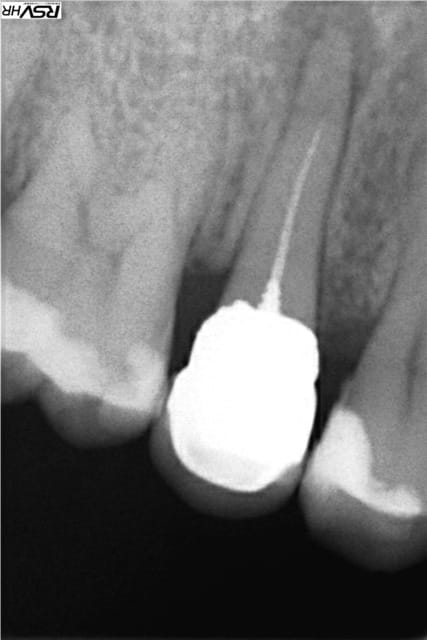

un post pour montrer que :reprise de traitement canalaire

sous digue+hypo+gutta compactée mac spaden peut fonctionner

RTE en 2013 ;guérison en 2015